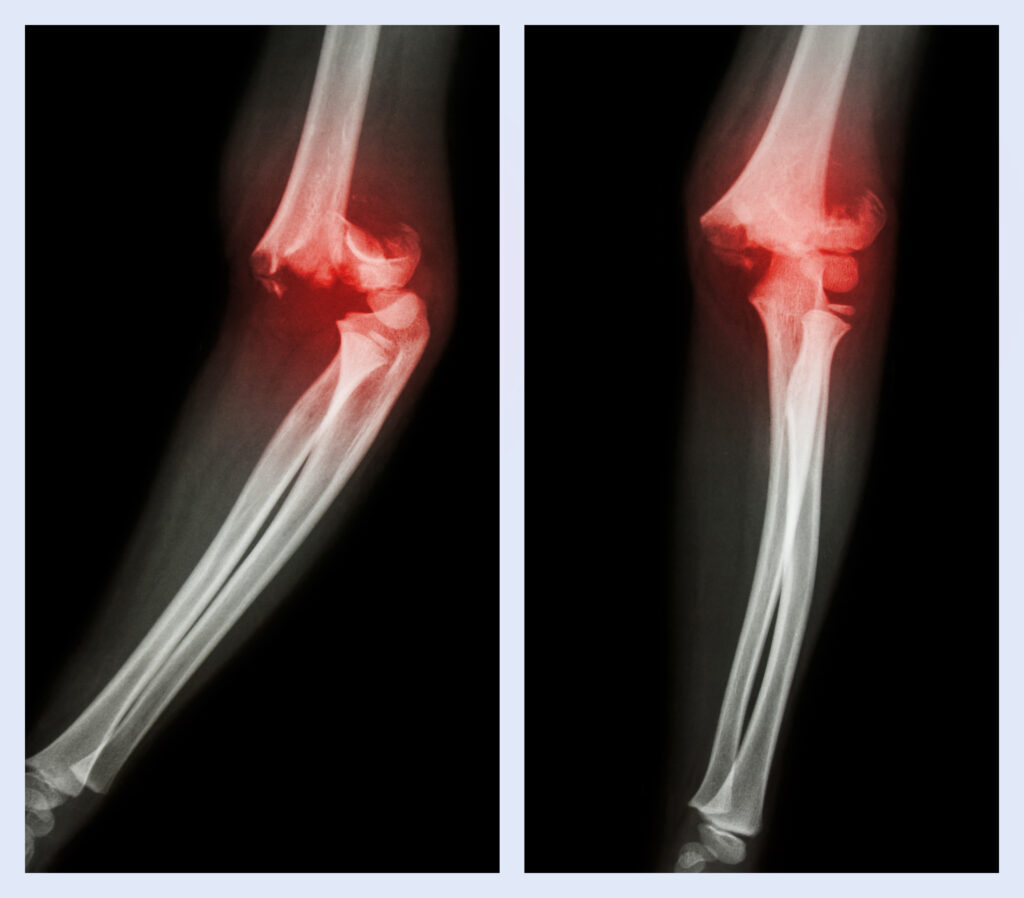

Elbow Dislocation

The radial head is the uppermost part of the radius bone in the forearm that forms part of the elbow joint. It allows for smooth rotation of the forearm and helps stabilize the elbow. Damage to this area can lead to pain, limited motion, and instability.